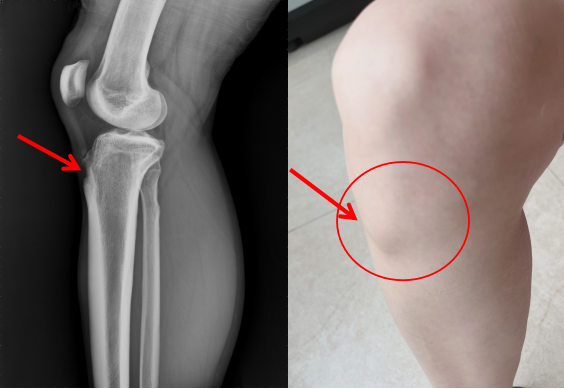

第二,肿胀。主要是胫骨结节处肿胀。轻者局部肿胀可不明显,但典型胫骨结节软骨炎患者,由于局部出现坏死、新骨形成、软组织无菌性炎症等,胫骨结节处隆起肿胀可较明显。

胫骨结节骨骺炎的主要X线检查表现为:1.局部软组织肿胀、密度增高。2.异位钙化;由于局部既有骨的坏死又有新骨的形成,特别是股四头肌附着点或肌腱处继发性钙化或者异位钙化。3.骨骺的改变;表现为骨骺密度增高,边缘不规则,部分骨骺破碎、分离。